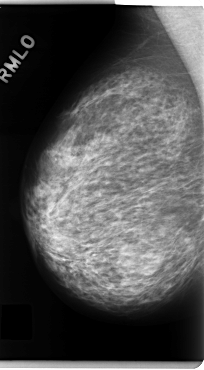

C_0130_1.RIGHT_MLO

RIGHT_MLO LINES 4808 PIXELS_PER_LINE 2648 BITS_PER_PIXEL 12 RESOLUTION 50 NON_OVERLAY